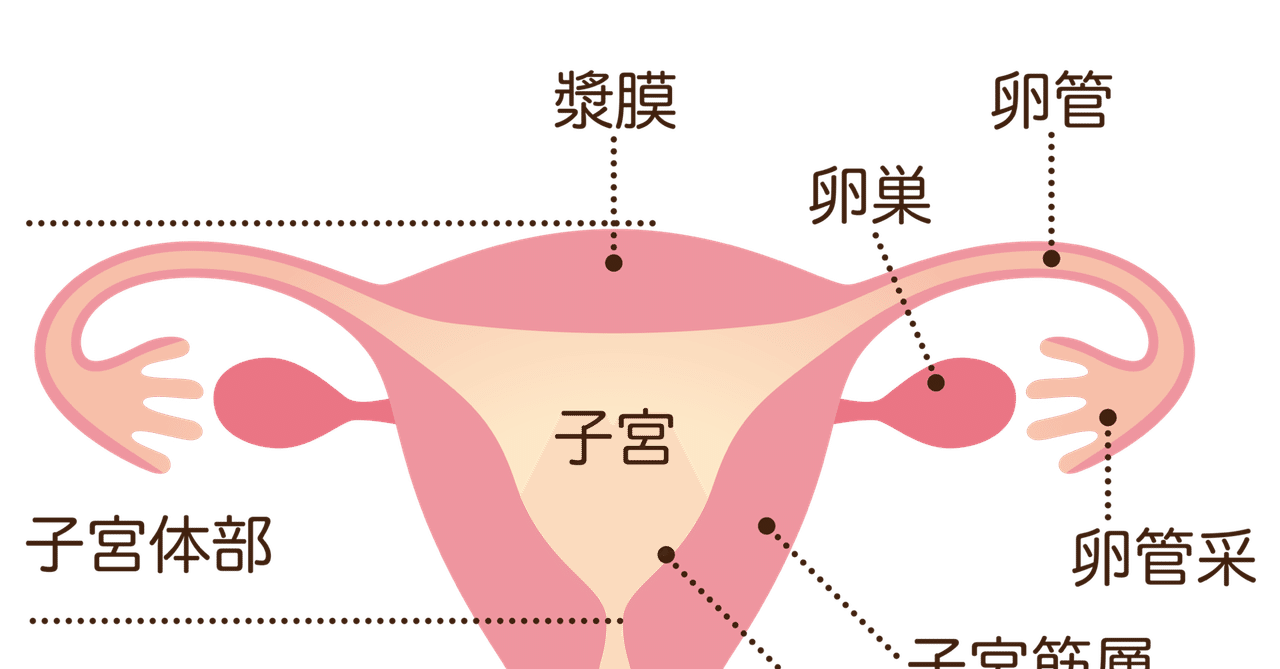

卵巣嚢腫、または卵巣嚢腫は、液体と空気で満たされた薄い膜で囲まれた泡のように見えます。骨盤領域の痛み、膨満感、腹部の重さ、月経の遅れ、または妊娠の困難を引き起こす可能性があります。

月経周期中、卵巣は通常、卵胞と呼ばれる嚢胞状の構造を形成し、ホルモンのエストロゲンとプロゲステロンを生成し、排卵するたびに卵子を放出します。正常な毎月の卵胞が成長を続ける場合、それは機能性嚢胞として知られます。

これらに加えて、月経周期に関係しない他のタイプの嚢胞もあります。

- 皮様嚢胞: 奇形腫とも呼ばれ、胚細胞から形成されるため、毛髪、皮膚、歯などの組織が含まれる場合があります。

- 嚢胞腺腫:卵巣の表面に発生し、水様物質または粘液で満たされています。

- 子宮内膜腫– 子宮内膜細胞が子宮の外で増殖するときに発生します(子宮内膜症)。組織の一部が卵巣に付着して嚢胞を形成する場合があります。